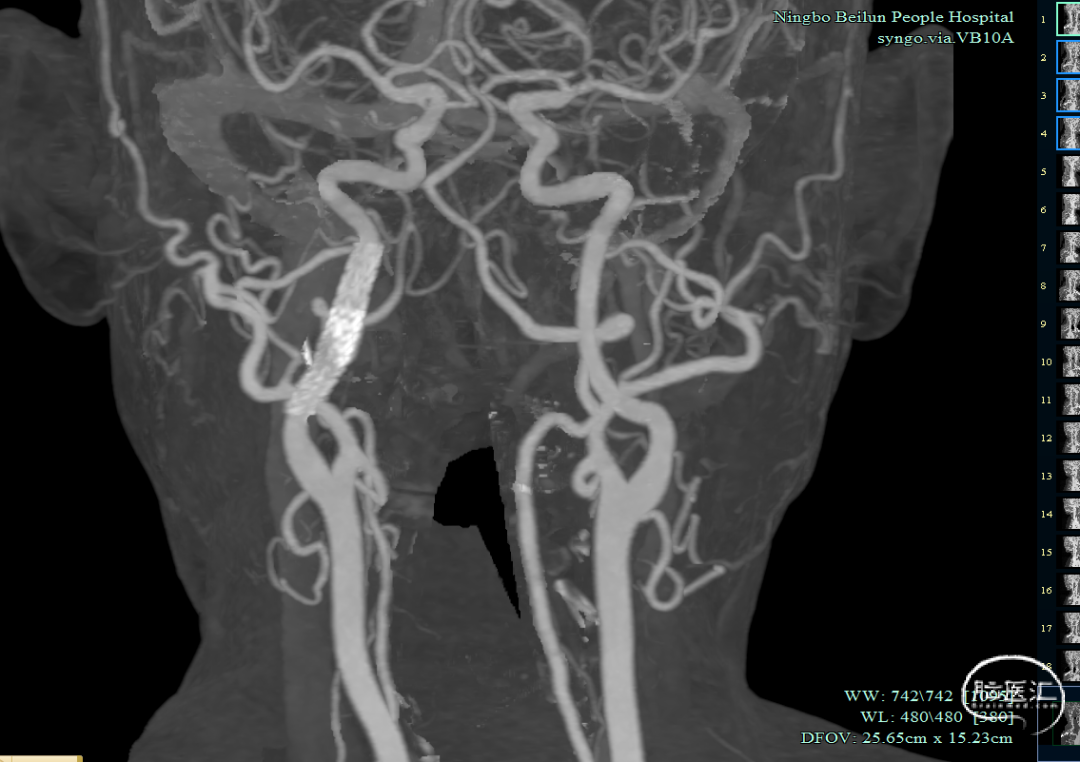

入院查体:神清,言语清晰,对答基本切题,双侧瞳孔等大圆形,对光反射灵敏,眼球向左、向上、向下运动不能,左侧鼻唇沟稍浅,口角右歪,伸舌左歪,左上肢肌力2-级,左下肢肌力3+级,右侧肢体肌力5级,双侧巴氏征阳性。NIHSS评分7分。头颅MRA:右侧颈内动脉闭塞。

为进一步评估梗死大小和颅内情况,磁共振显示颈内动脉闭塞,小的核心梗死。

术后三个月随访:mRS 0分,颈部血管CTA显示支架形态良好。